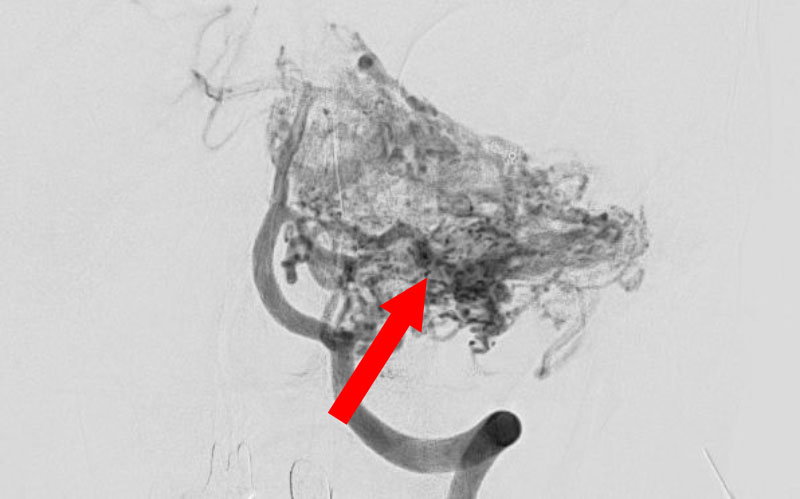

No.1620 手術前